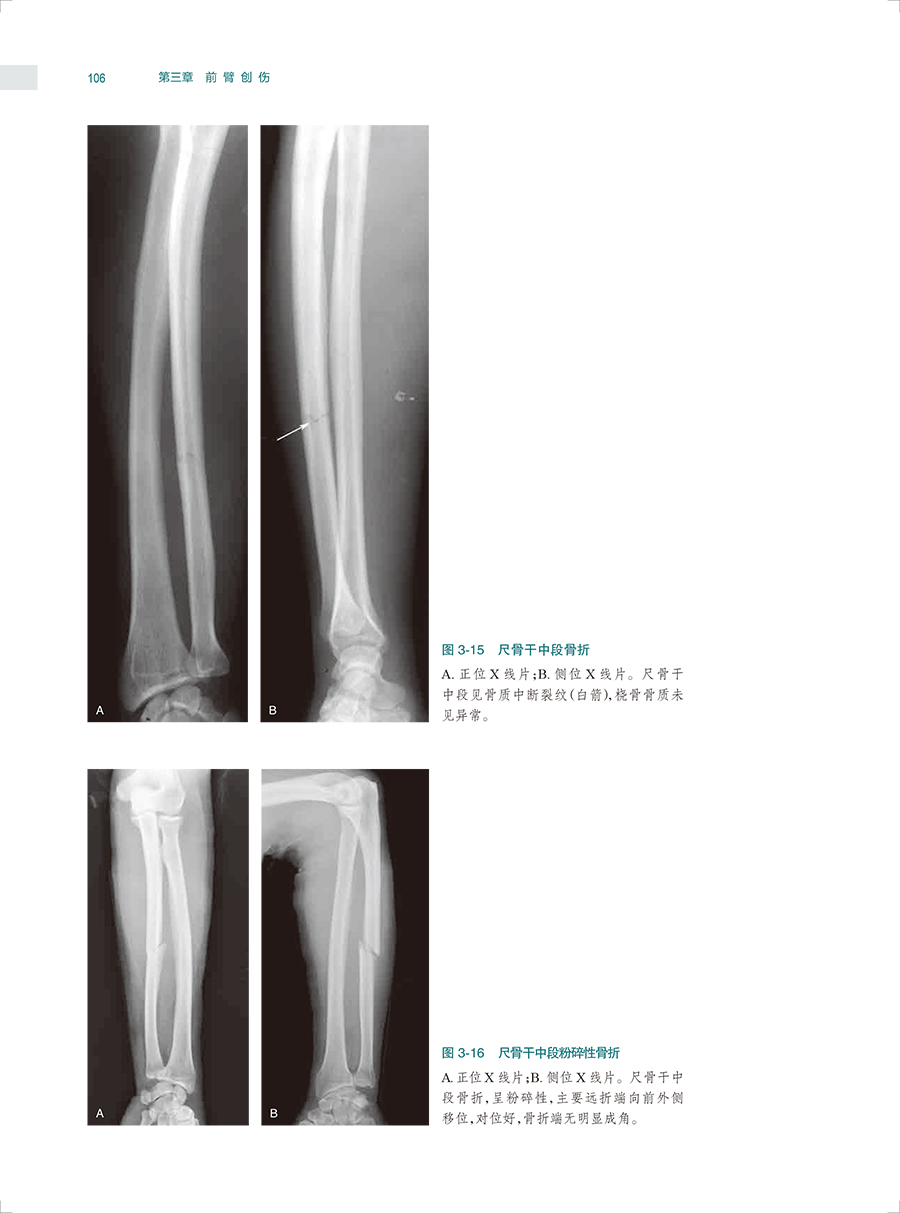

本书是一本系统全面介绍骨关节创伤X线诊断的图谱专著。全书共十六章,前十五章每章基本按创伤类型、诊断要点和鉴别诊断体例编写,最后一章介绍常见骨关节创伤后遗症及并发症。书中共选用1270幅X线照片图,约760个病例,所选图片和病例均具有代表性,可使读者对各部位、各类型的骨关节创伤及其后遗症和并发症有进一步认识,从而提高诊断水平。本书主要供骨科医生、影像科医生使用。